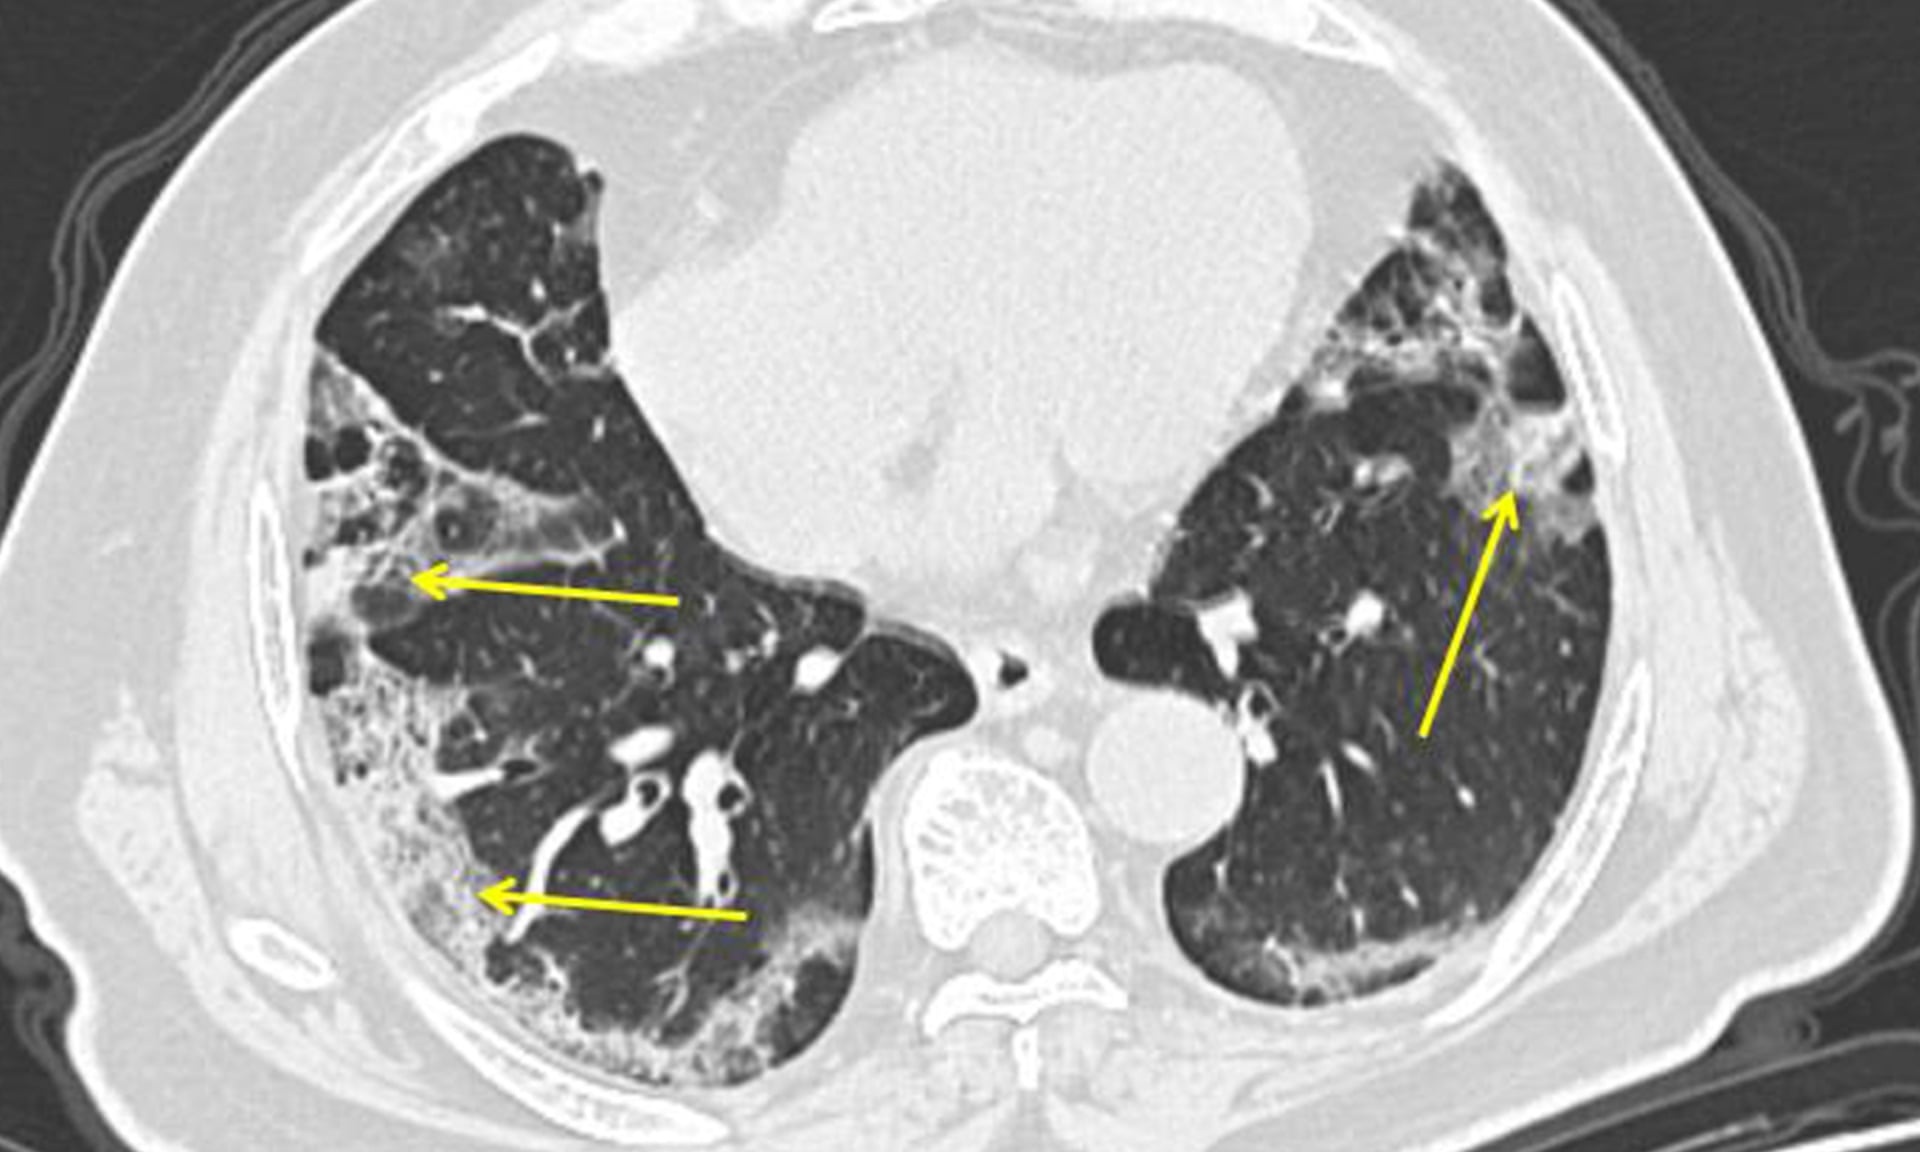

Các chuyên gia giải thích rằng các trường hợp tử vong do Covid-19 thường là do viêm phổi, đồng thời giải thích cơ chế virus gây ra viêm phổi ở người cao tuổi, người có bệnh nền.